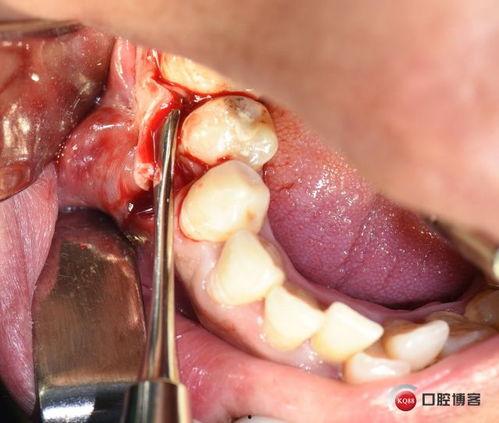

2. 手术过程

手术过程中,医生会小心翼翼地将囊肿内的液体吸出来,然后用一种叫做“根管治疗”的方法,将牙齿内部的细菌彻底清除。他们会用一种叫做“根尖诱导剂”的物质,填充到根尖部分,防止囊肿再次复发。